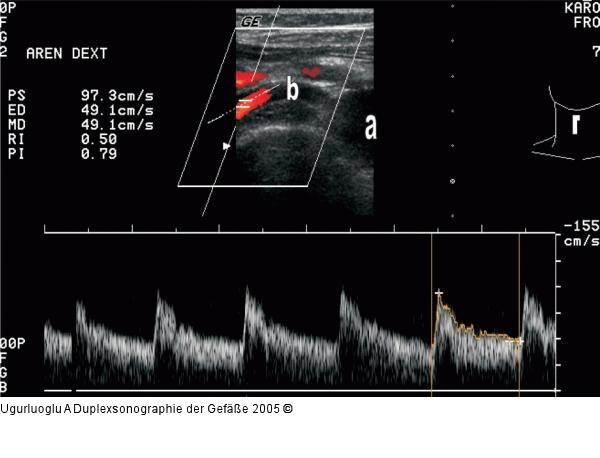

Abbildung 7: Duplexsonographie - Pulsdoppler Bogenförmiger Abgang der Arteria renalis dext. aus der Aorta abdominalis. Transversale Schnittführung. a) Aorta abdominalis, b) Arteria renalis dext. Die Dopplerflußanalyse zeigt eine holodiastolische Strömung als Zeichen eines niedrigen peripheren Widerstandes. RI 0,50. |

Abbildung 7: Duplexsonographie - Pulsdoppler